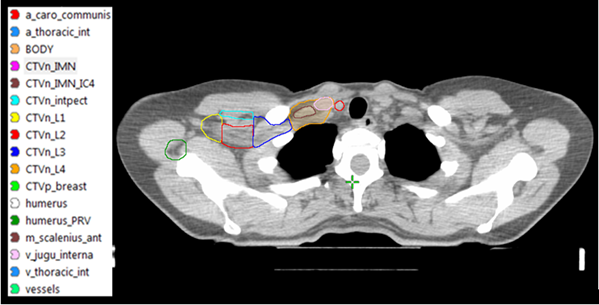

Figur 3. CTVN enligt ESTRO consenus guideline [4]. Inritningen av lymfkörtelvolymerna underlättas genom att vissa landmärken i form av vener och artärer definieras.